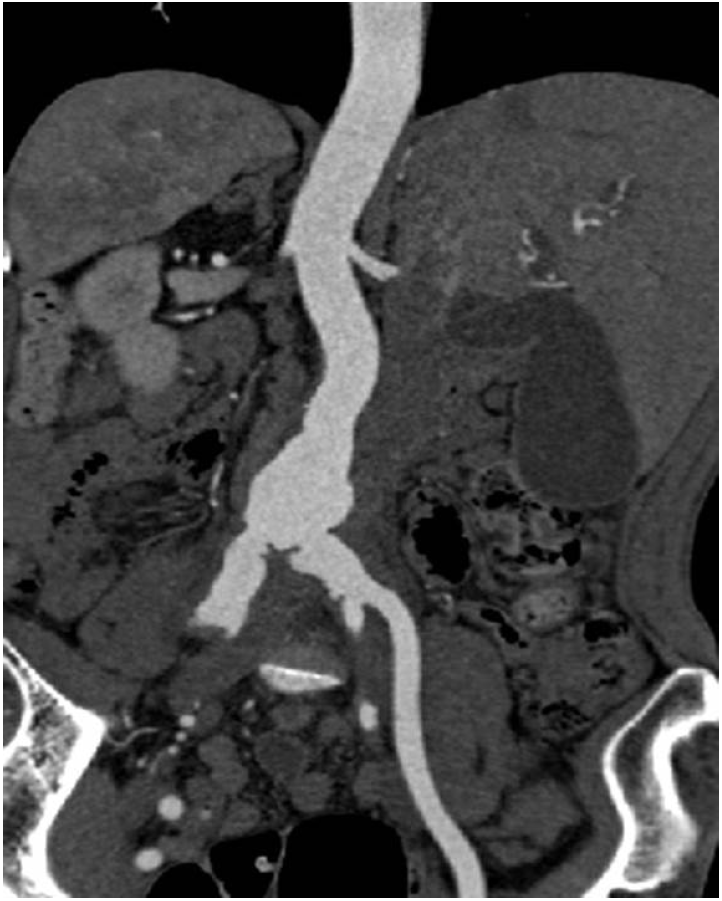

Figure 1.

Abdominal computed tomography shows irregular aortic and vascular aneurysmal dilation (maximum diameter: 3.2 cm) from the lower abdominal aorta to both common iliac arteries.

Figure 2.

Computed tomography angiography shows aneurysmal dilation of the upper end of the abdominal aorta and the left common iliac artery.